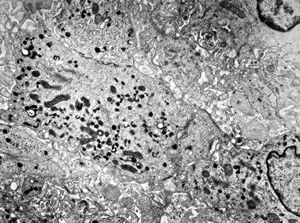

M,10y. | herpetic encephalitis